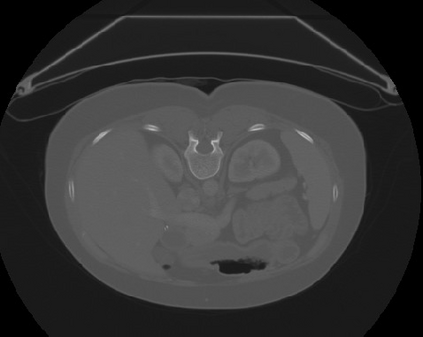

Transformers, the default model of choices in natural language processing, have drawn scant attention from the medical imaging community. Given the ability to exploit long-term dependencies, transformers are promising to help atypical convolutional neural networks (convnets) to overcome its inherent shortcomings of spatial inductive bias. However, most of recently proposed transformer-based segmentation approaches simply treated transformers as assisted modules to help encode global context into convolutional representations without investigating how to optimally combine self-attention (i.e., the core of transformers) with convolution. To address this issue, in this paper, we introduce nnFormer (i.e., Not-aNother transFormer), a powerful segmentation model with an interleaved architecture based on empirical combination of self-attention and convolution. In practice, nnFormer learns volumetric representations from 3D local volumes. Compared to the naive voxel-level self-attention implementation, such volume-based operations help to reduce the computational complexity by approximate 98% and 99.5% on Synapse and ACDC datasets, respectively. In comparison to prior-art network configurations, nnFormer achieves tremendous improvements over previous transformer-based methods on two commonly used datasets Synapse and ACDC. For instance, nnFormer outperforms Swin-UNet by over 7 percents on Synapse. Even when compared to nnUNet, currently the best performing fully-convolutional medical segmentation network, nnFormer still provides slightly better performance on Synapse and ACDC.